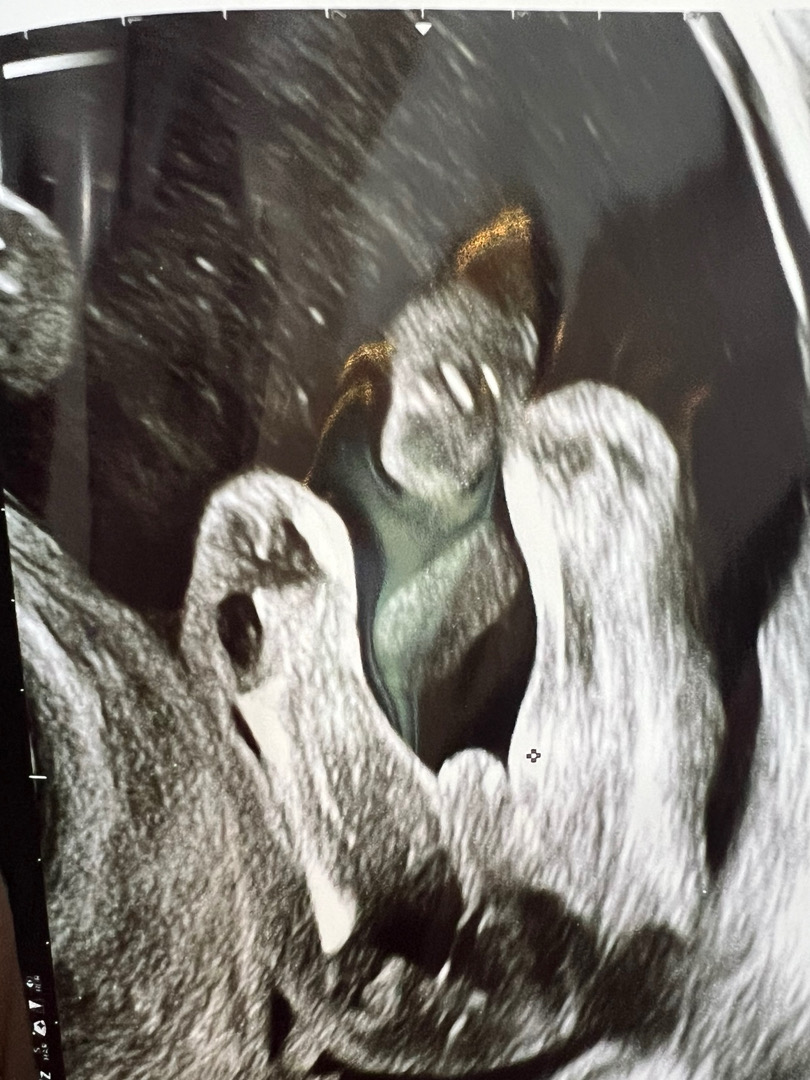

16주 초음파,, 한번 봐주세용~~!

아들인것같은데 애매하게 나오기두 할까요,,,ㅎㅎ

딸 같아요!! 아들은 진짜 존재감 뿜뿜..

저16주3일 아들 확정받았는데 오줌나오는 선까지 되게 그냥 나 고추야!!! 이런느낌이에용!! 탯줄 말려보이는걸수도있을것같아요!

딸같은데여? 아들은 진짜 또렷한 모양이에요!16주면 병원에서 알려주셨을것 같은데 뭐라셔요?

뭐가 보이시죠..? 아들같네요! 하셨는데,, 정확한건 21주때 다시 보자고는 하셨러요ㅠㅠ